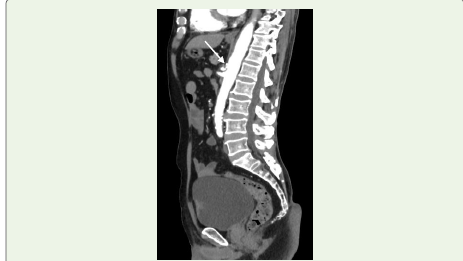

Figure 2:A 77-year-old man evaluated for haematuria and diagnosed with

bladder carcinoma (white arrow). Incidentally noted on sagittal contrast enhanced

CT angiography is a kinked proximal celiac artery with a hooked

contour and associated post-stenotic dilatation.